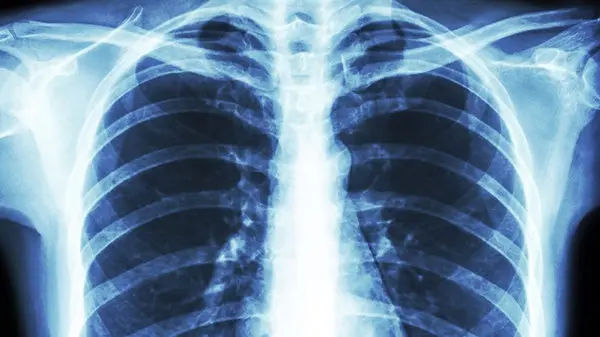

به گزارش رکنا، دکتر علی معینی با اشاره به درگیری ریه ها در بسیاری موارد ابتلا به کرونا گفت: در مواردی که ابتلا به کرونا در حد متوسط و یا شدید است، درگیری ریه ها به عنوان یکی از عوارض بیماری دیده می شود که میتواند بعضا خطرناک باشد.

وی افزود: درگیری ریه ها در بیماری کرونا بطور معمول با علائمی چون سرفه و تنگی نفس خود را نشان میدهد و اینطور نیست که ریه ها درگیر شده و فرد بدون علامت باشد.

معینی گفت: البته مواردی داریم که در افرادی که دچار علائم خفیف کرونا شده اند بعد از سه تا چهار روز به یکباره ریه ها درگیری شدید پیدا کرده و حتی منجر به فوت بیمار میشود که این امر بسته به سن افراد مبتلا و قدرت سیستم ایمنی بدن آنها و وجود برخی بیماریهای زمینه ای دارد.

این متخصص بیماری های عفونی خاطرنشان کرد: در همین راستا مراجعه سریع به پزشک با وجود علائم خفیف بسیار حائز اهمیت است و بهتر است افراد در صورت داشتن علائم خفیف برای تشخیص کرونا تست PCR بدهند و در صورتی که علائمی مانند سرفه و تنگی نفس دارند توصیه می شود از سی تی اسکن برای تشخیص میزان درگیری ریه ها استفاده کنند.

معینی با اشاره به پایدار بودن عوارض کرونا گفت: در برخی مبتلایان کرونا مواردی داریم که افراد پس از بهبودی کامل همچنان علائمی مانند سرفه و تنگی نفس دارند و باید گفت این سرفه ها و این تنگی نفس دیگر علائم کرونا نیستند، بلکه عوارض به جا مانده از این بیماری میباشند.

وی افزود: این عوارض که شامل درگیری ریه، قلب، مغز و ... میتواند باشد، بعد از بهبودی کامل هم امکان پیشروی و بدتر شدند دارند و این امکان هست که افراد پس از بهبودی از کرونا به سمت نارسایی تنفسی بروند، بنابراین درمان این عوارض باید تحت نظر پزشک معالج دنبال شود.